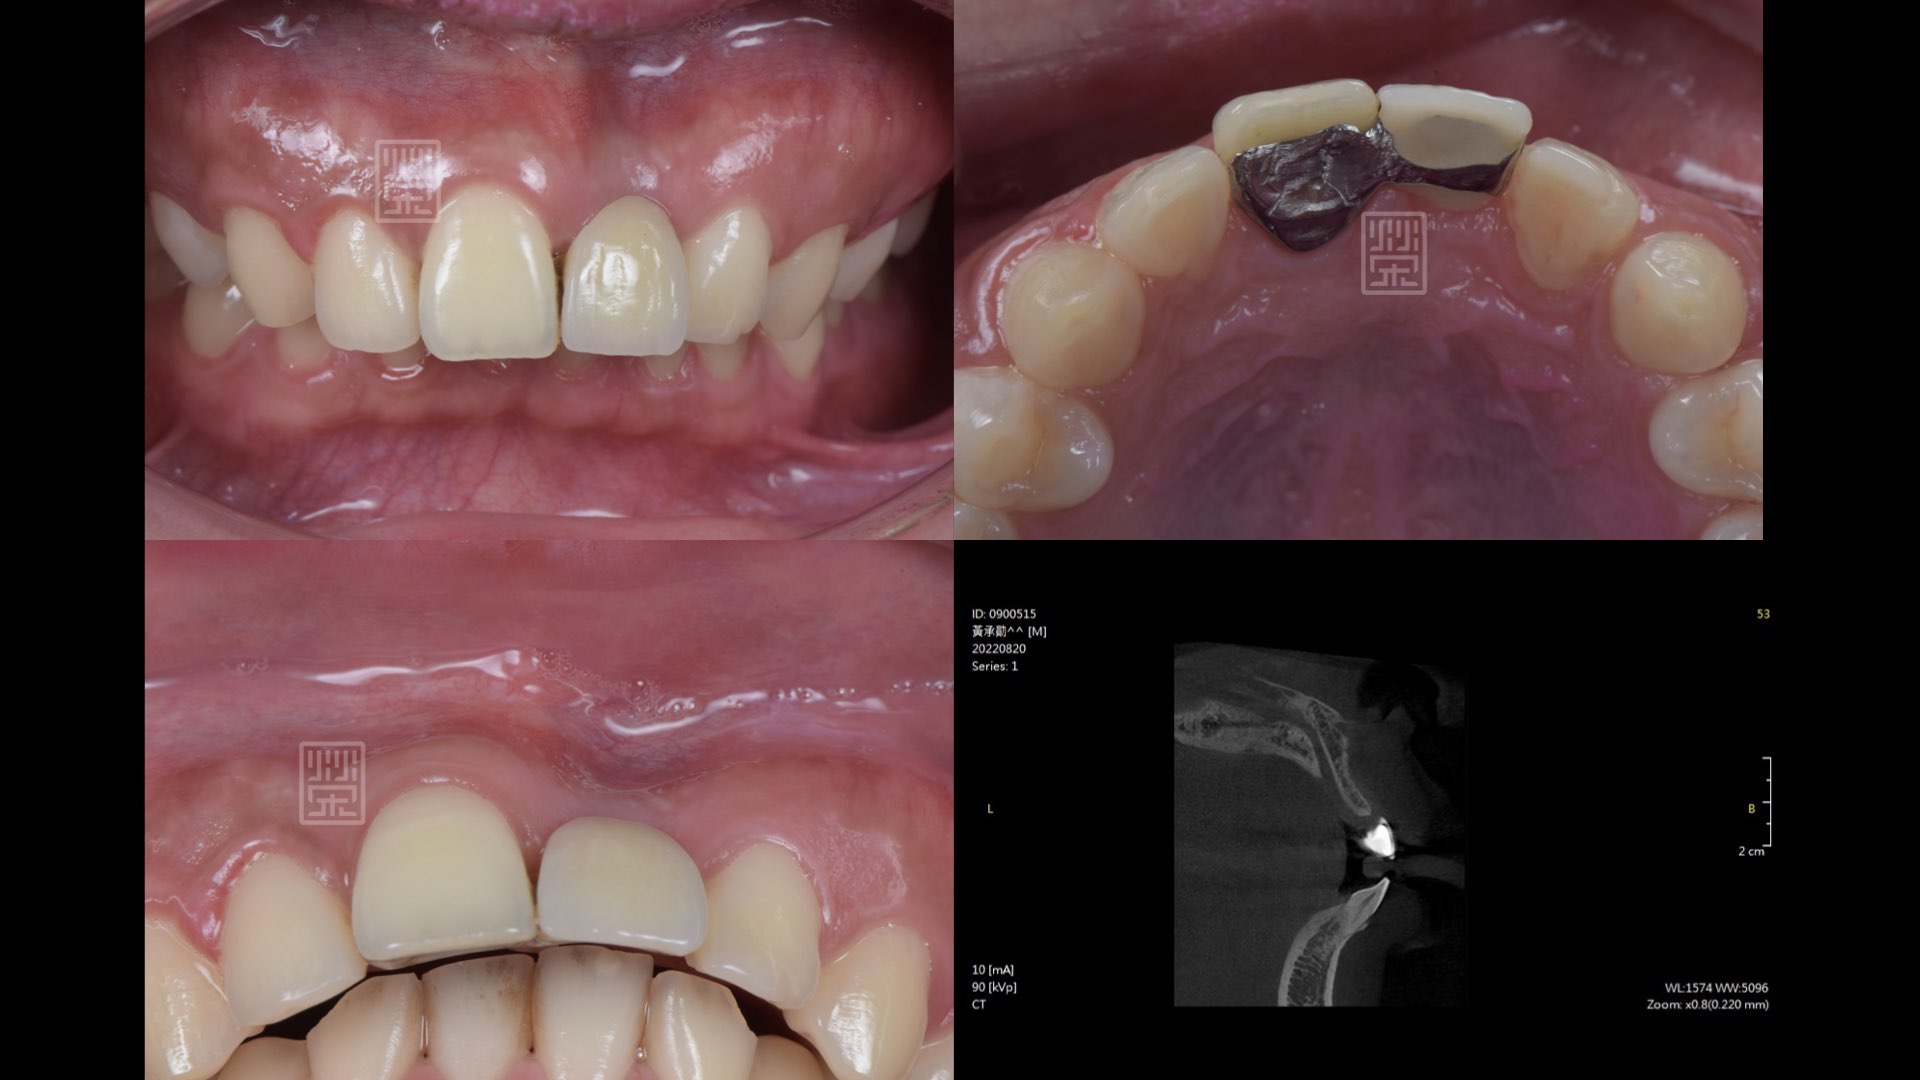

2022年他回診時說,榮醫師,我要出國唸書了,我想把牙齒完成。中間經歷了他當兵,完成了補骨、植牙、補肉,在出國前夕,完整將治療完成。

感謝陳昭明醫師與吳禕凡醫師手把手教學sausage, ti-mesh骨再生,讓我有機會可以完成十年前與小男孩的承諾。

治療十二年後馬利蘭牙橋

初次補骨

植牙與再次補骨